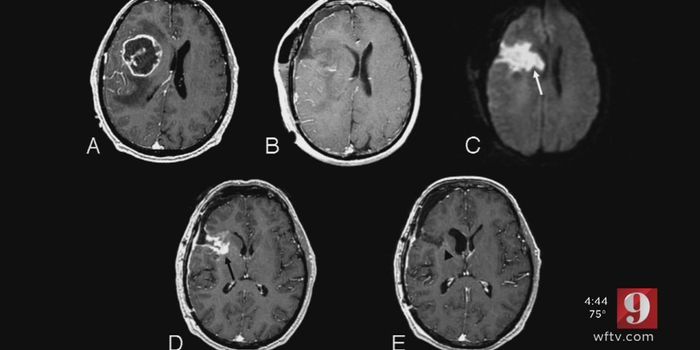

JAN 01, 2018VideosA rare form of brain cancer that strikes mostly children under the age of 10 years old seems centered in a particular ar ...

AUG 31, 2017VideosIn children, brain cancer is the number one cause of cancer-related deaths. Brain tumors are extremely aggressive and of ...